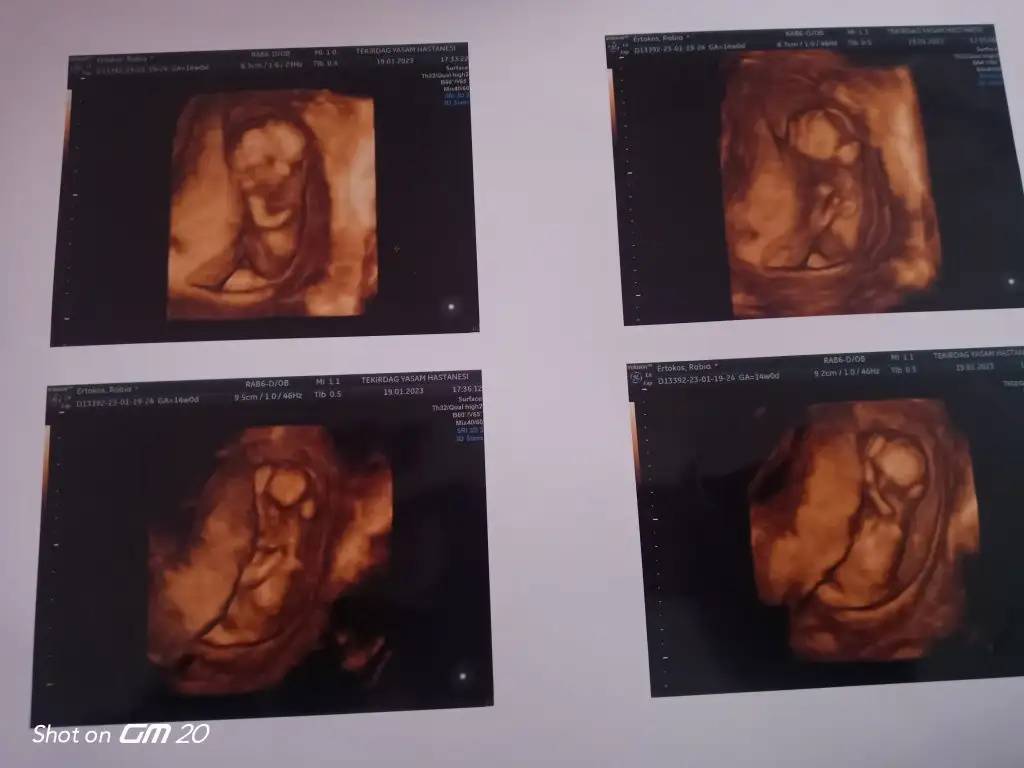

Bebişiniz erkek zaten doktorun elinize tutuşturduğu fotoğrafta pipisi gözüküyor Rabbim sağlıkla kucağınıza aldırsın oğluşunuzu

Erkek benceEki Görüntüle 3207494 merhaba ilk fotoğrafta 7 haftalık tam ikinci 9 haftalık karından ikiside çok merak ediyorum cinsiyetini tahminde bulunur musunuz şuan 10+1 olduk